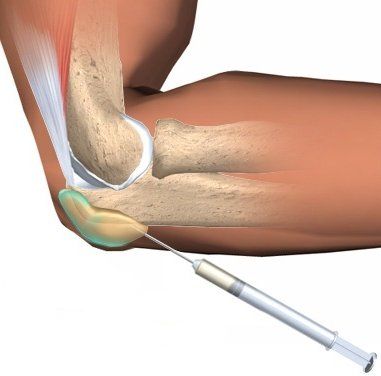

При прогрессировании заболевания и увеличении бурсы в размерах проводится пункция синовиальной сумки с аспирацией содержимого и вводится в её полость раствор глюкокортикостероидов для снятия воспаления. Инъекция кортикостероидов значительно снижает продолжительность симптомов и число повторных аспираций [8].

Введение кортикостероидов в бурсу